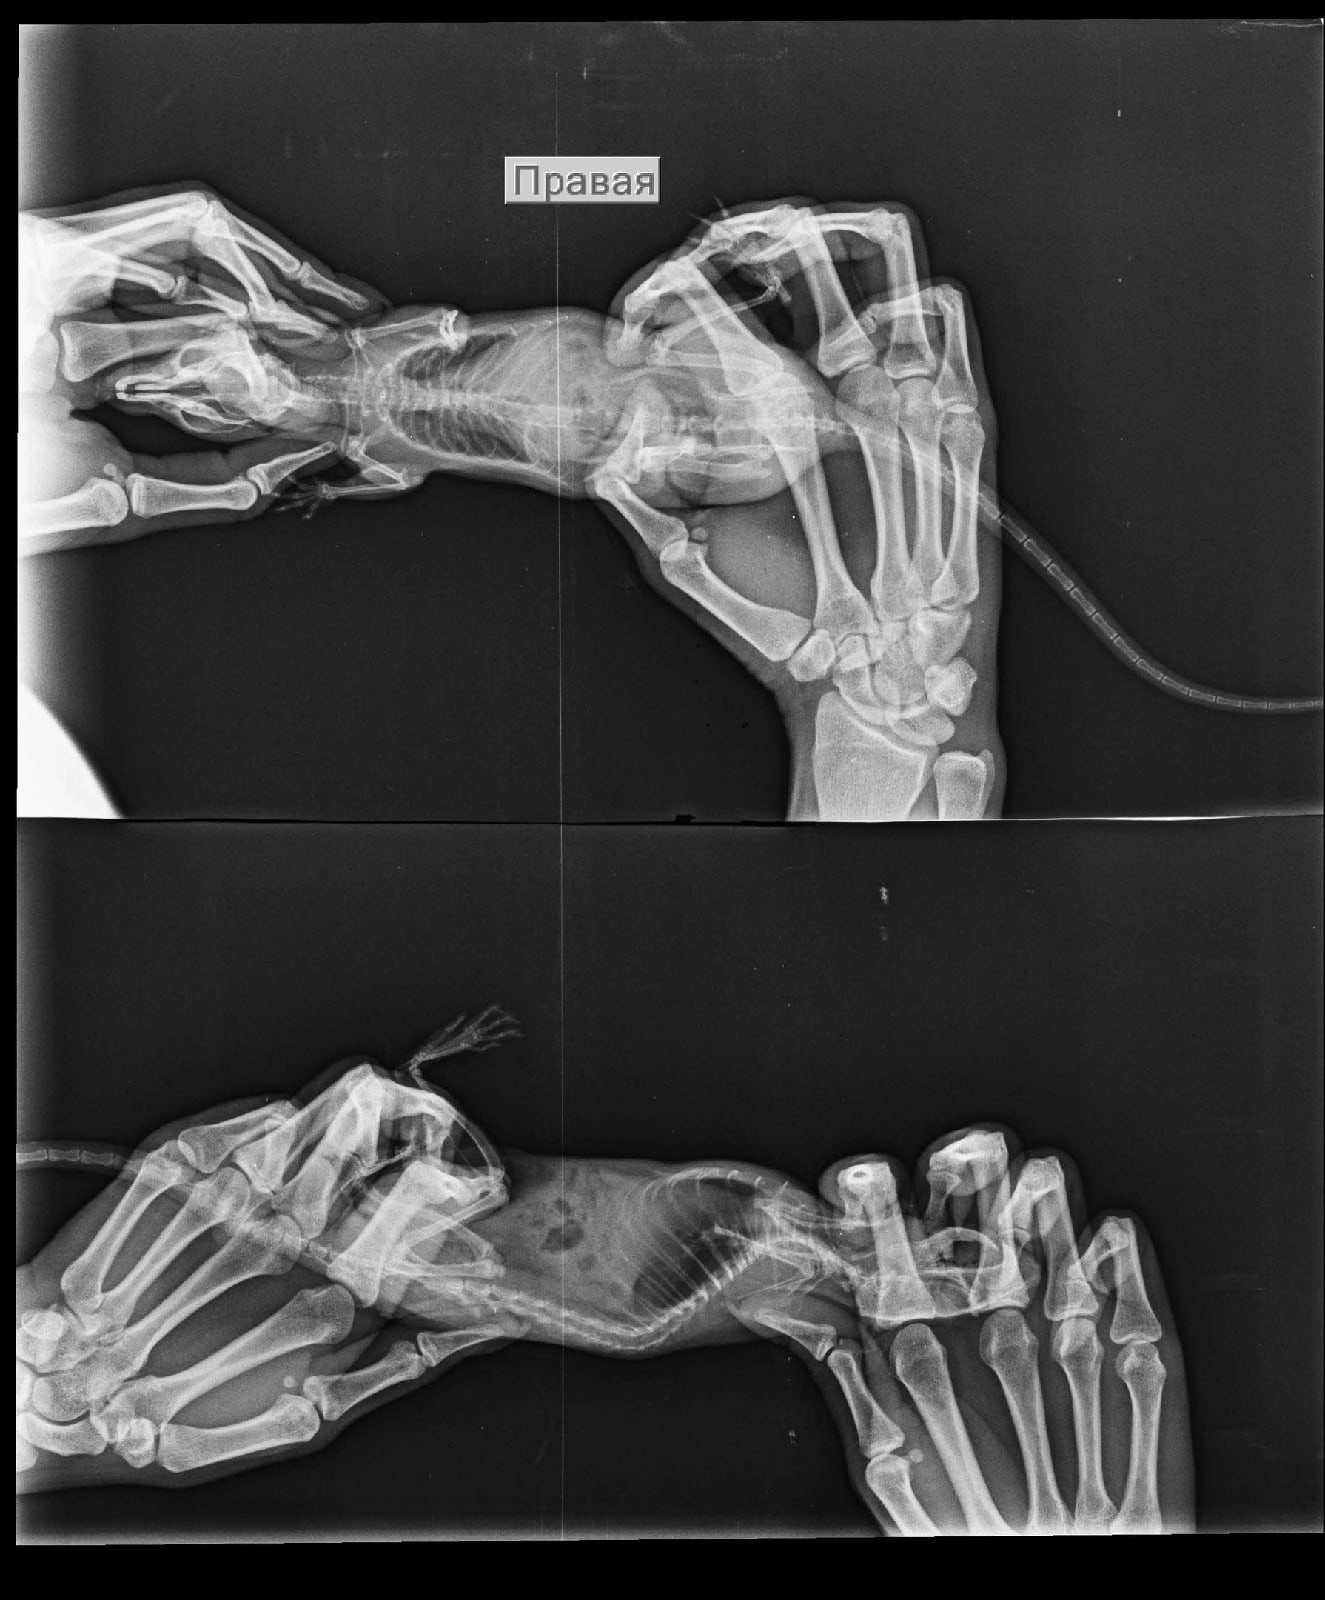

Добрый вечер, дополним историю лечения: лечились небулайзером беродуал 1мл + 4мл физраствор и ципрофлоксацин 50/50 с физраствором. Довольно долгое время. Ещё прикрепляем старые рентгены.

Вложения

r79B2LOR8LM.jpg

EAhluMIaX38.jpg

EAhluMIaX38.jpg (172.14 КБ) 33617 просмотров